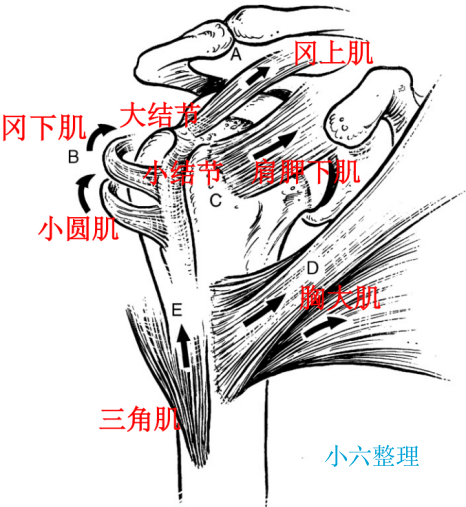

解剖

第三部分是小结节和附着的肩胛下肌,具有内收和内旋的作用;

第四部分是肱骨干,从外科颈或结节下水平断裂。